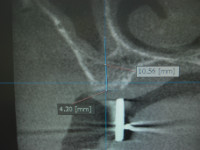

5/28日施術分オペ画像

この画像も5月28日施術分のオペ画像になります。

すでに下顎には複数本のインプラントを埋入され快調にご使用されているとのことで、上顎にもインプラントによる義歯固定の治療を希望されましたので3番相当部は抜歯即時で埋入し6番相当部にはソケットリフト法を併用しましてインプラントを問題なく埋入いたしました。